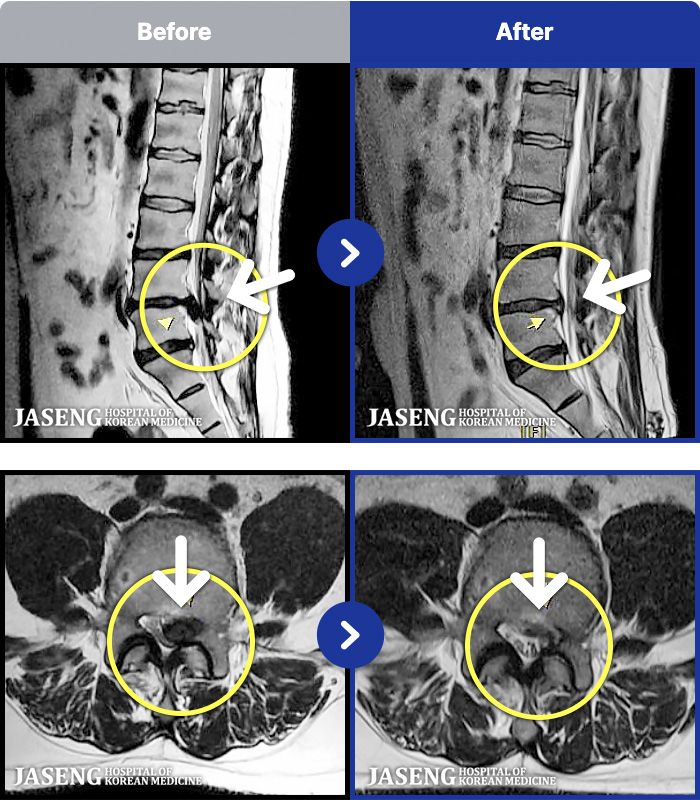

MRI ġ

MRI ũ ʸ Ȯϼ.